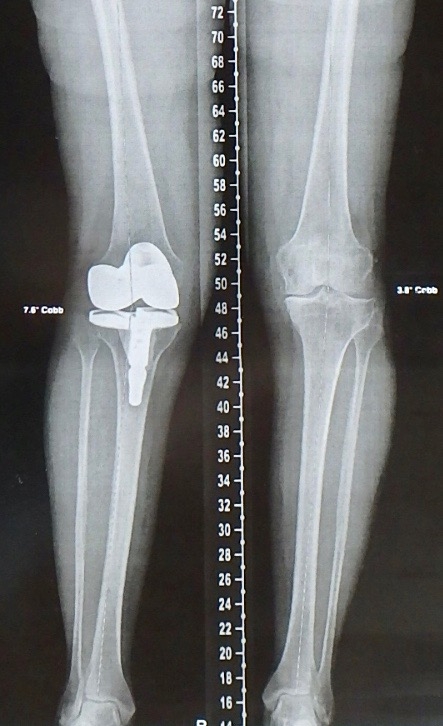

Radio des deux genoux après Prothèse Totale du Genou droit de Simone (radio prise le 14 décembre 2017, 3 mois après l’opération).